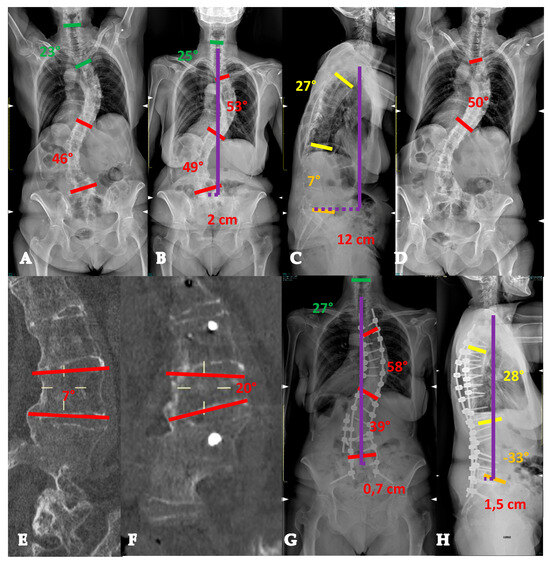

- For curves < 90° OR ≥90° and with a flexibility index > 15% (YADIS 2A), a combination of strategies with an all-posterior approach, already published by the authors under the acronym HiPoAD (High-Density Pedicle Screws, Ponte Osteotomies, Asymmetric Rods Contouring, Direct Vertebral Rotation) [10], may be sufficient to address the deformity. In particular, high-density constructs are preferrable in order to dissipate the corrective forces on every level and decrease the pull-out risks. Then, an aggressive posterior release based on multiple asymmetric Ponte osteotomies is of paramount importance, in order to allow an optimal deroto-translation over two asymmetrically contoured rods (Figure 3) [10,11].